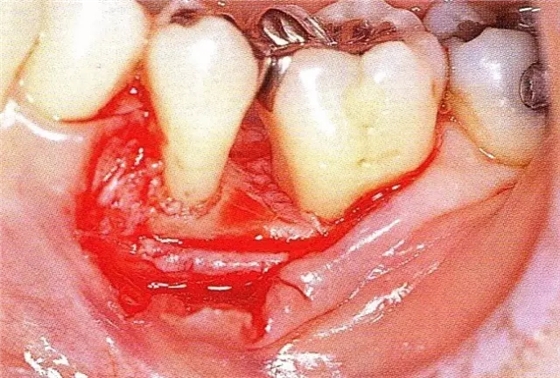

▲圖7-4術(shù)后1年2個(gè)月再翻開看的情況。與圖7-1的骨缺損狀態(tài)相比可知形成了臨床性骨再生。

▲圖7-5此狀態(tài)下,左下5的遠(yuǎn)中存在牙槽骨不平整,因此進(jìn)行了骨修整。同時(shí),將骨膜留存,進(jìn)行了齦瓣根尖側(cè)移動(dòng)術(shù),去除了牙周袋。